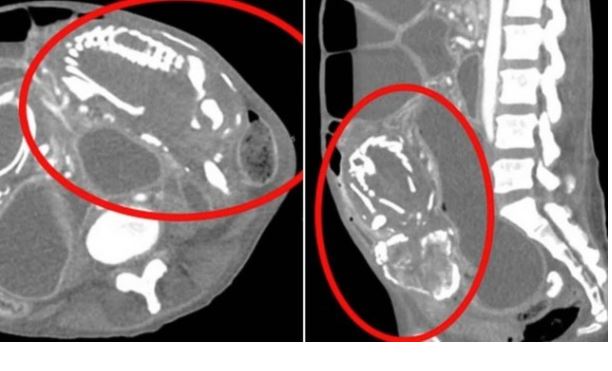

Exames mostraram que ela tinha um feto calcificado, também conhecido como "bebê de pedra", alojado dentro dos seus intestinos, o que a estava causando obstrução intestinal grave e subseqüente desnutrição.

No entanto, a este fenômeno é dado o nome de litopédio, registrado 290 vezes em toda a história, e que ocorre quando feto começa a se desenvolver no abdômen e não no útero, fazendo com que ele se calcifique e "vire pedra" e absorve os nutrientes da mãe.